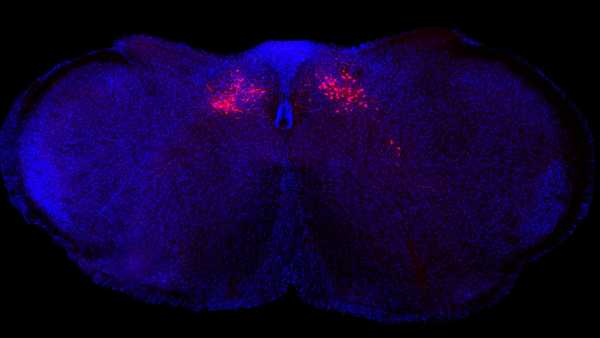

По-друге, дослідники проаналізували загальнодоступні генетичні дані понад 61 000 окремих Т-клітин, взятих з тканини мозку, пошкодженої розсіяним склерозом. Вони шукали, які гени були надмірно активними, і виявили багато тих самих генів, які були виявлені у пацієнтів, що тестувалися на наявність розсіяного склерозу, а також інші, пов'язані із запаленням.